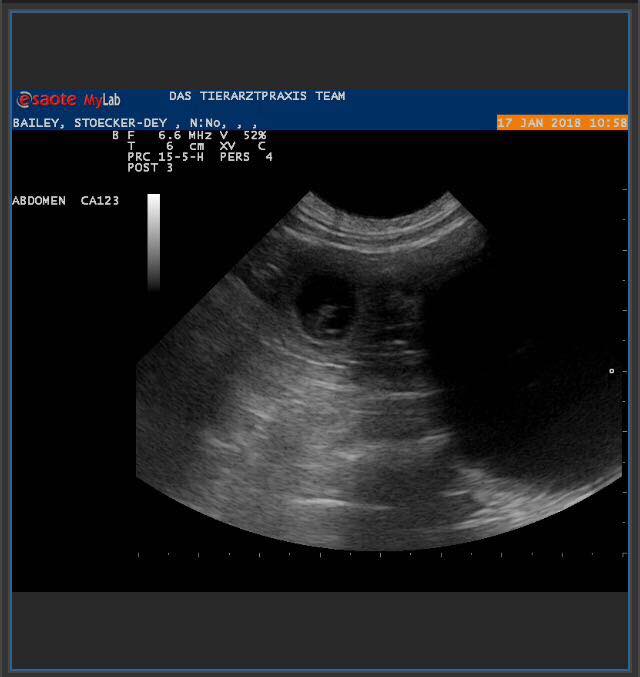

| 4. Woche | Am 22. Tag sind die Embryonen sichtbar. Der Herzschlag kann zur Diagnose der Trächtigkeit herangezogen werden. Anstrengende Aktivitäten sind jetzt zu vermeiden.Die Proteinzufuhr im Futter kann erhöht werden. Hierfür eignet sich sehr gut die Gabe von Welpenfutter. Zu diesem Zeitpunkt kann mit einer Ultraschalluntersuchung der Zustand der Trächtigkeit festgestellt werden. Besprechen Sie mögliche Risiken einer solchen Untersuchung mit dem Tierarzt. |

| Mi, 17.01.2018 bis So, 21.01.2018 | Dies ist der beste Zeitpunkt, um die Trächtigkeit anhand des Herzschlags zu diagnostizieren. Die Embroynen sind etwas walnussgroß und sind gleichmäßig im Uterus verteilt. |